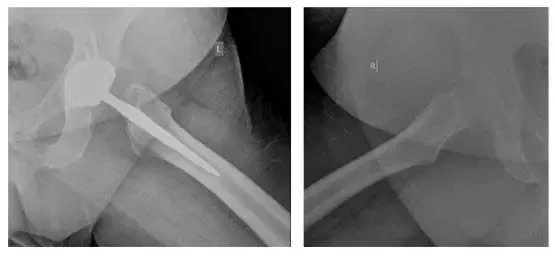

X-rays of Bilateral Hips. Four views were taken: AP Pelvis (top left), Left AP Hip (top right), Left Lateral Frog (bottom left), Right Lateral Frog (bottom right).

X-rays reveal osteolysis in the acetabulum with possible loosening of the femoral component. Loosening is best seen on comparison with earlier X-ray.